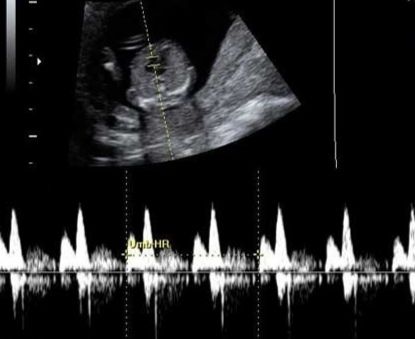

ЧСС 157 уд/мин (я засняла на телефон, чтобы мужу дать послушать, пока он в командировке)

Очень похоже на девочку. Не знаю что там этот Рамзи... Его метод 60 на 40 работает, а по кардиограмме сердечко бьется двойным ударом - как у девочек. Было 2 разнополых Б, у сына билось отчётливо, и на снимке было видно, будто ряд ромбиков...

А у дочери один стук дублировался 2 раза.